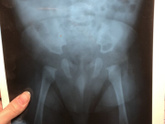

Девчат среди нас есть ортопеды?или те кто немного в этом шарит ?снимки сделаны в три(голубой)и в семь(серый)месяцев ,у нас только отсутствуют ядра окостенения или дисплазия (смещение ,вывих,подвывих)тоже есть ?завтра иду к врачу ,но все равно мучаюсь … Читать далее